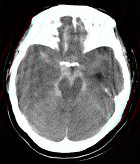

- 单项选择题成年男性,外伤后一小时出现头痛, 呕吐,查体: 颈项强直。CT检查如图,最可能的诊断是 ( )

A、硬膜外血肿

B、脑出血

C、正常脑CT

D、硬膜下血肿

E、蛛网膜下隙出血